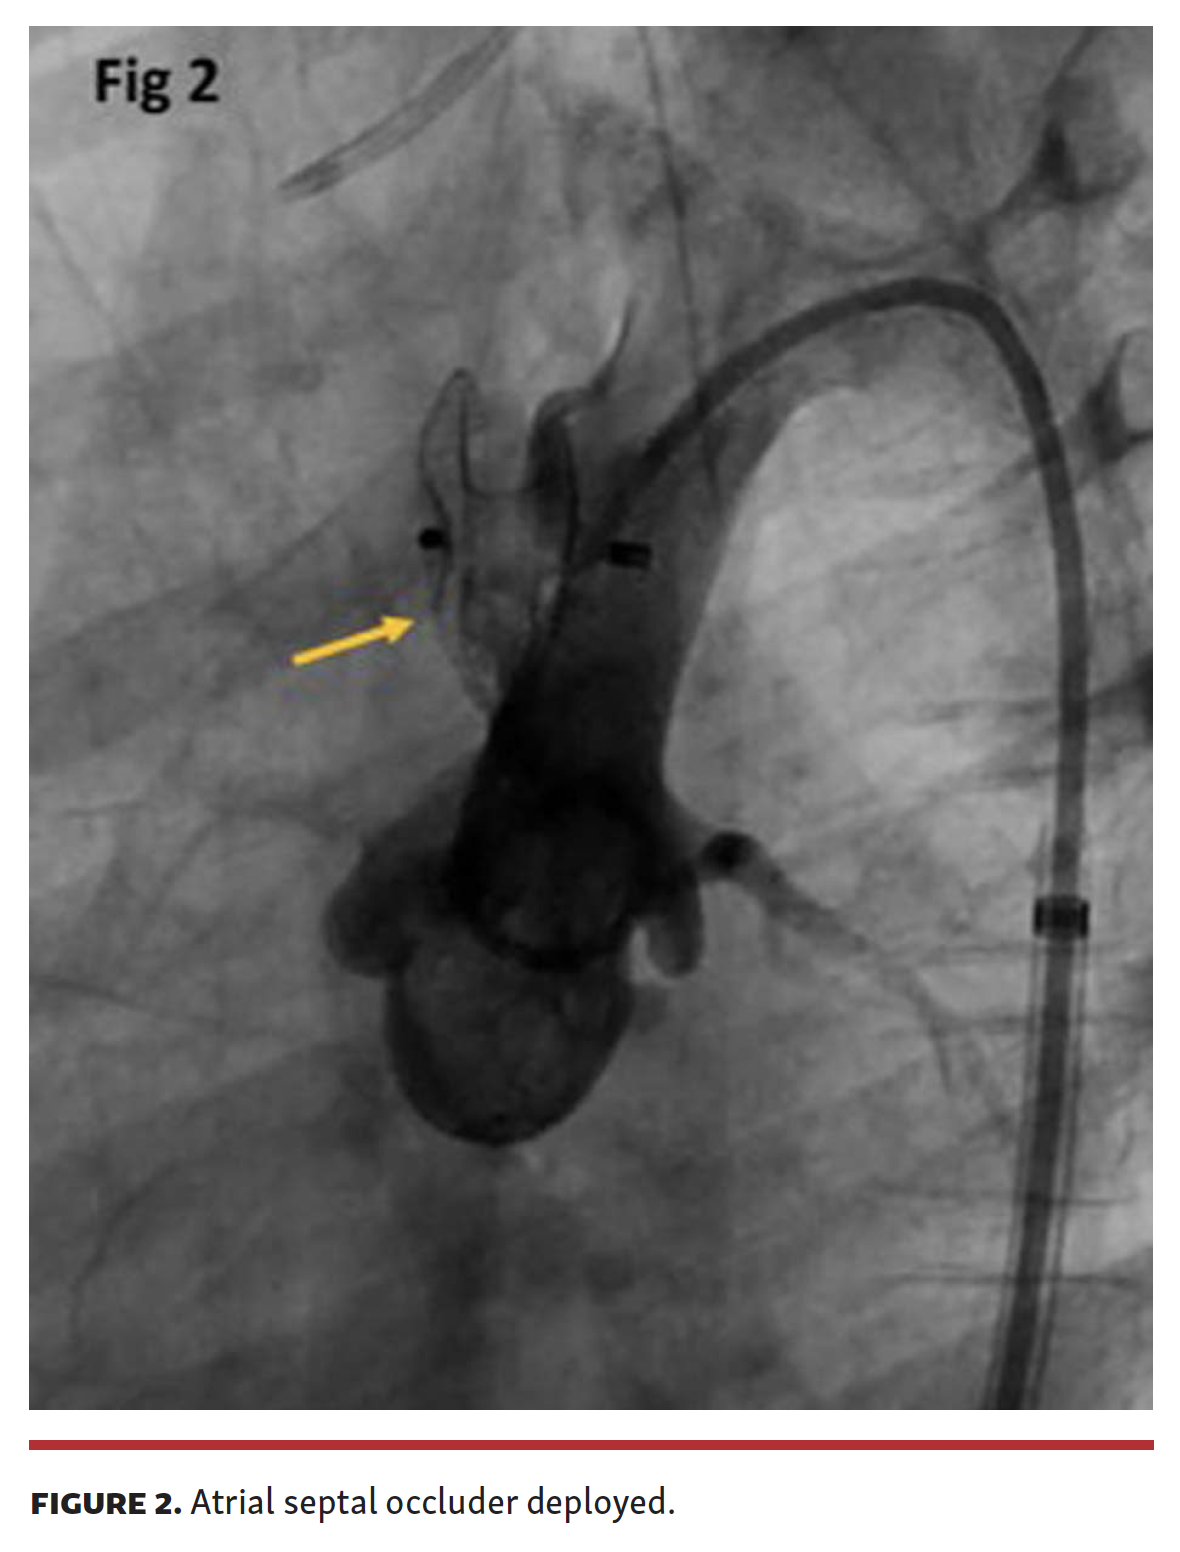

Aortic root angiogram was performed (Video 2) and a 7 Fr Mullins sheath (Medtronic) was placed in the aneurysm sac over a 0.035˝ Glidewire (Terumo), without injuring the walls of the aneurysm. The aneurysm was closed with an 8 mm Amplatzer atrial septal occluder (Abbott) (Figure 2; Video 3). After stabilization, the patient underwent patch aortoplasty a few days later, as we did not want to leave behind a device in the presence of active endocarditis. At 1-year follow-up, the patient was doing well.